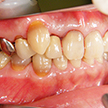

5. 初診時右側

八重歯を中心とした叢生が顕著です。その周囲のみが既にクラウンとなっており、不適合が目立ちます。

6. 初診時左側

右側の八重歯が相当飛び出しているのが目立ちます。これでは口唇を咬みそうです。閉口障害となり同部が乾燥して良好な環境ではありません。治療方針として八重歯を何とかしたいと考えます。